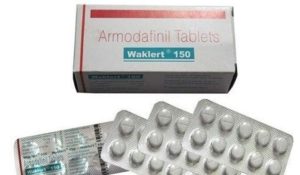

Supplements

When should you stop taking ZMA Sleep?

ZMA Sleep is a supplement that has been used to improve sleep quality in people for many years. However, recent […]